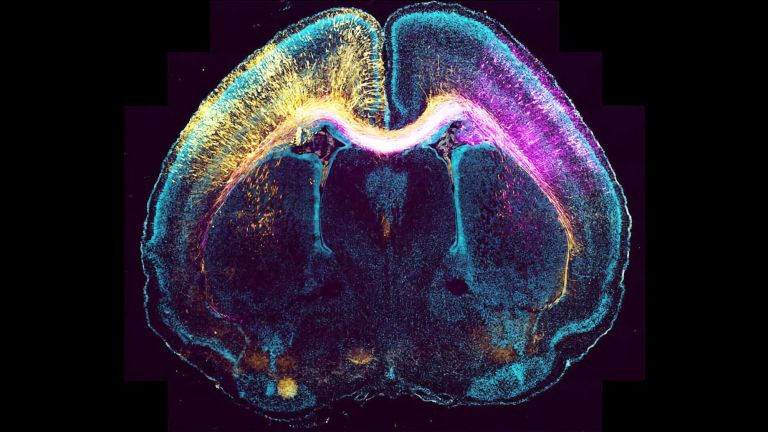

Das pubertierende Gehirn löst sich zwar nicht auf, aber es kommt ihm zunehmend graue Substanz abhanden, also die Anteile im Gehirn, die vornehmlich aus Nervenzellkörpern bestehen. Vor allem der Cortex dünnt sich ab ungefähr dem 10. Lebensjahr stark aus . Das liegt weniger an absterbenden Zellen als daran, dass massenhaft Synapsen, die Kontaktstellen zwischen den Zellen, verloren gehen – und zwar vor allen solche, die wenig genutzt werden. Gleichzeitig nimmt die weiße Substanz im Gehirn weiter zu: Oligodendrozyten, eine besondere Form von Gliazellen, umwickeln immer mehr Axone. Die so gebildete fettreiche Myelinscheide, die der weißen Substanz auch ihre Farbe verleiht, erlaubt es den Axonen, Signale bis zu dreitausend mal schneller zu übertragen.

Der Frühjahrsputz unter den während der Kindheit verschwenderisch gebildeten Synapsen und die aufgemotzten Axone sorgen für mehr Effizienz im jugendlichen Gehirn. Doch diese stellt sich keineswegs überall gleichzeitig ein. Stattdessen folgen die Umbauarbeiten einer komplexen Choreographie, die auch Erklärungen für absonderliches Teenagergebaren anbieten. Die Generalüberholung arbeitet sich nämlich von schlichteren zu komplexeren kognitiven Funktionen vor. Sie beginnt mit acht oder neun Jahren im sensorischen und motorischen Cortex im Scheitellappen, die Sinne und motorischen Fähigkeiten zu schärfen und erfasst dann ab ungefähr dem 10. Geburtstag Bereiche im Stirnlappen, die für Koordinierungsaufgaben zuständig sind, zum Beispiel für sprachliche Ausdrucksfähigkeit und räumliche Orientierung.

Als letztes ziehen im Stirn- und Schläfenlappen diejenigen Regionen nach, die eine besonders wichtige Rolle bei höheren, integrativen kognitiven Funktionen wie z. B. der Willensbildung, Handlungsplanung und Impulskontrolle spielen. Besonders wichtig für solche Vernunft-Leistungen ist der präfrontale Cortex, und gerade dieser entwickelt sich besonders langsam, bis über den 20. Geburtstag hinaus. Jugendliche lassen sich zum Beispiel bei Denkaufgaben noch deutlich leichter ablenken als Erwachsene und zeigen dabei vor allem im präfrontalen Cortex andere Aktivitätsmuster.

Die Spätzündung im präfrontalen Cortex bedeutet auch, dass sich früher entwickelnde, emotional betonte Gehirnregionen in der Pubertät vergleichsweise ungezügelt austoben können. Männliche und weibliche Geschlechtshormone leisten dazu einen direkten Beitrag, vor allem im limbischen System, das eine wichtige Rolle bei der Verarbeitung von Emotionen und der Steuerung von Impulsen spielt und viele Hormonrezeptoren vorweisen kann. Testosteron fördert das Wachstum der Amygdala (des Mandelkerns), Östrogen eher das des Hippocampus . Beide Regionen sind Teil des Belohnungssystems, und die Amygdala wirkt als emotionaler Verstärker, gerade wenn es um Angst oder Wut geht.

Wie genau hormonelle Veränderungen die Struktur und Funktion dieser Gehirnregionen beeinflussen, ist zwar noch längst nicht klar, aber gerade die Amygdala gilt als heißer Kandidat für einen Motor pubertären Verhaltens . Bestens vernetzt mit anderen Gehirnarealen mischt sie vermutlich bei vielen Jugendexzessen mit – seien es Stimmungsschwankungen, erhöhte Aggression, Furchtlosigkeit und Risikofreude oder die Suche nach aufregenden Kicks. In der Amygdala nimmt die graue Substanz bei Teenagern entgegen dem Trend sogar zu – insbesondere bei Jungs, die schließlich auch mehr Testosteron produzieren. Bessere kognitive Leistungen gehen mit einem massiven Mandelkern nicht unbedingt einher, mitunter sogar das Gegenteil. Jedenfalls die Erkennung von Gesichtern und Gefühlen anderer – eine weitere wichtige Funktion der Amygdala – klappt in der Pubertät zeitweise weniger gut als in der Kindheit oder im Erwachsenenalter.